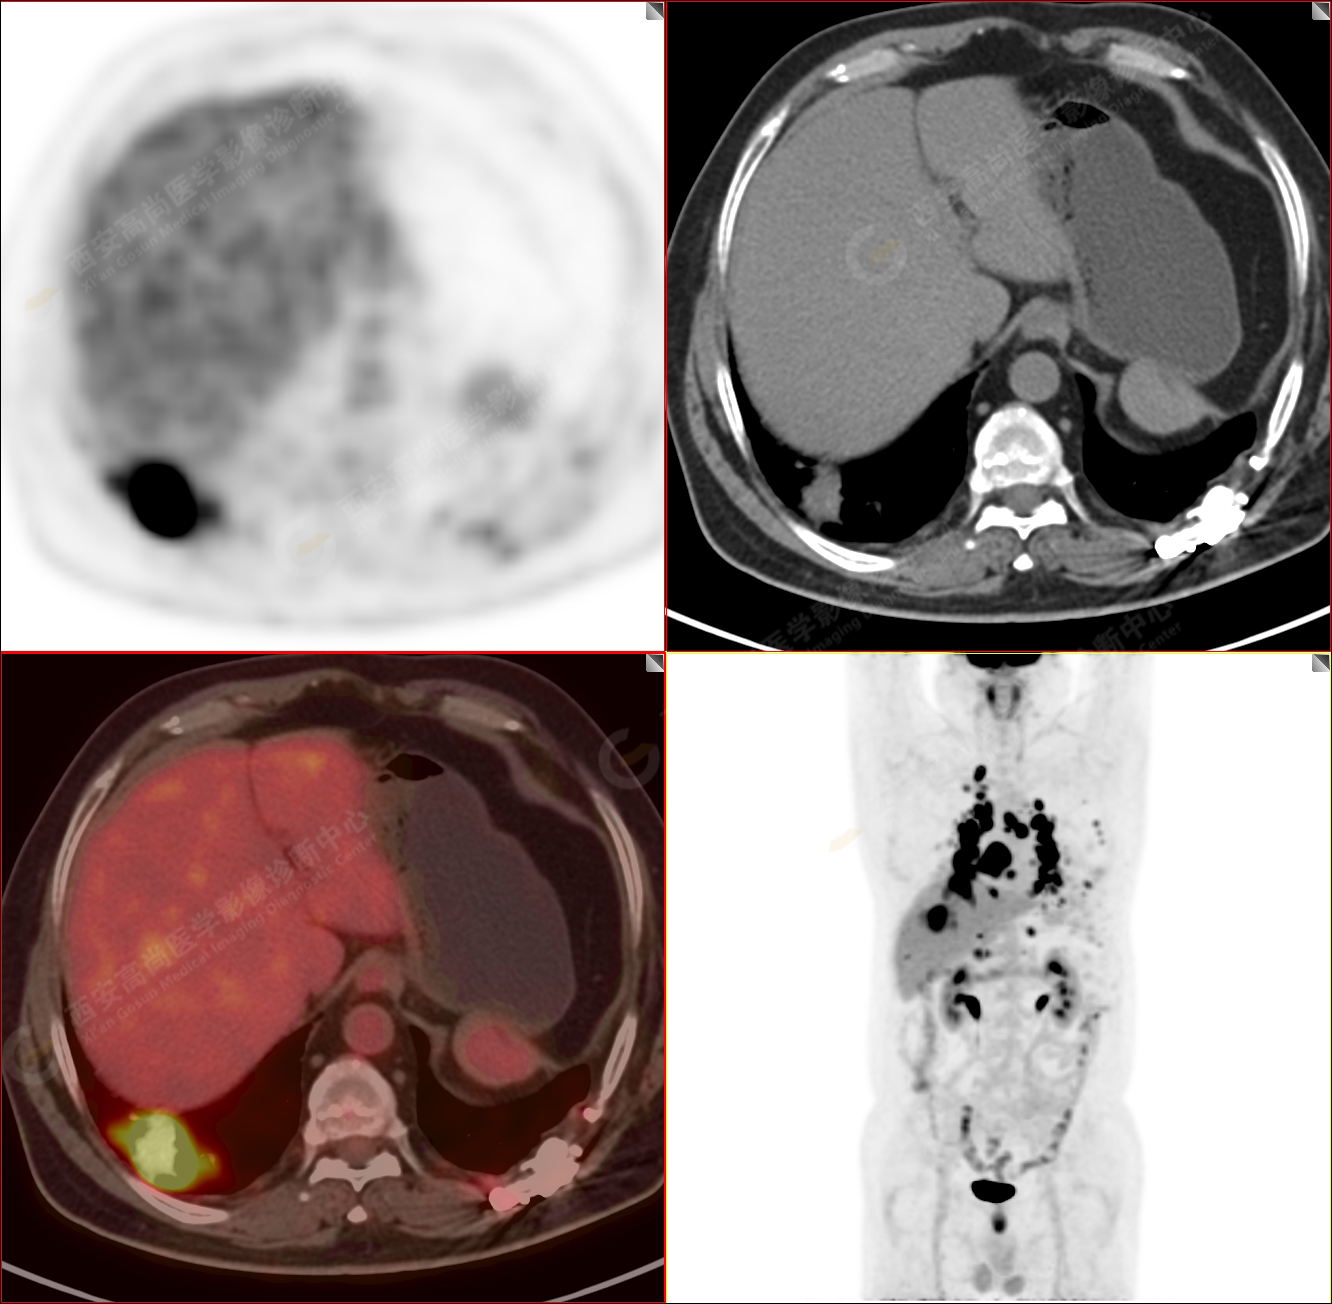

男性,53歲,頭暈半月入院,CT發(fā)現(xiàn)肺內(nèi)腫塊,雙肺多發(fā)大小不等實(shí)性及粟粒樣結(jié)節(jié),雙肺門(mén)及縱隔多發(fā)腫大淋巴結(jié)。病程中無(wú)發(fā)熱、胸悶氣及胸部不適。既往:左側(cè)肋骨外傷史。

PET-MR圖像